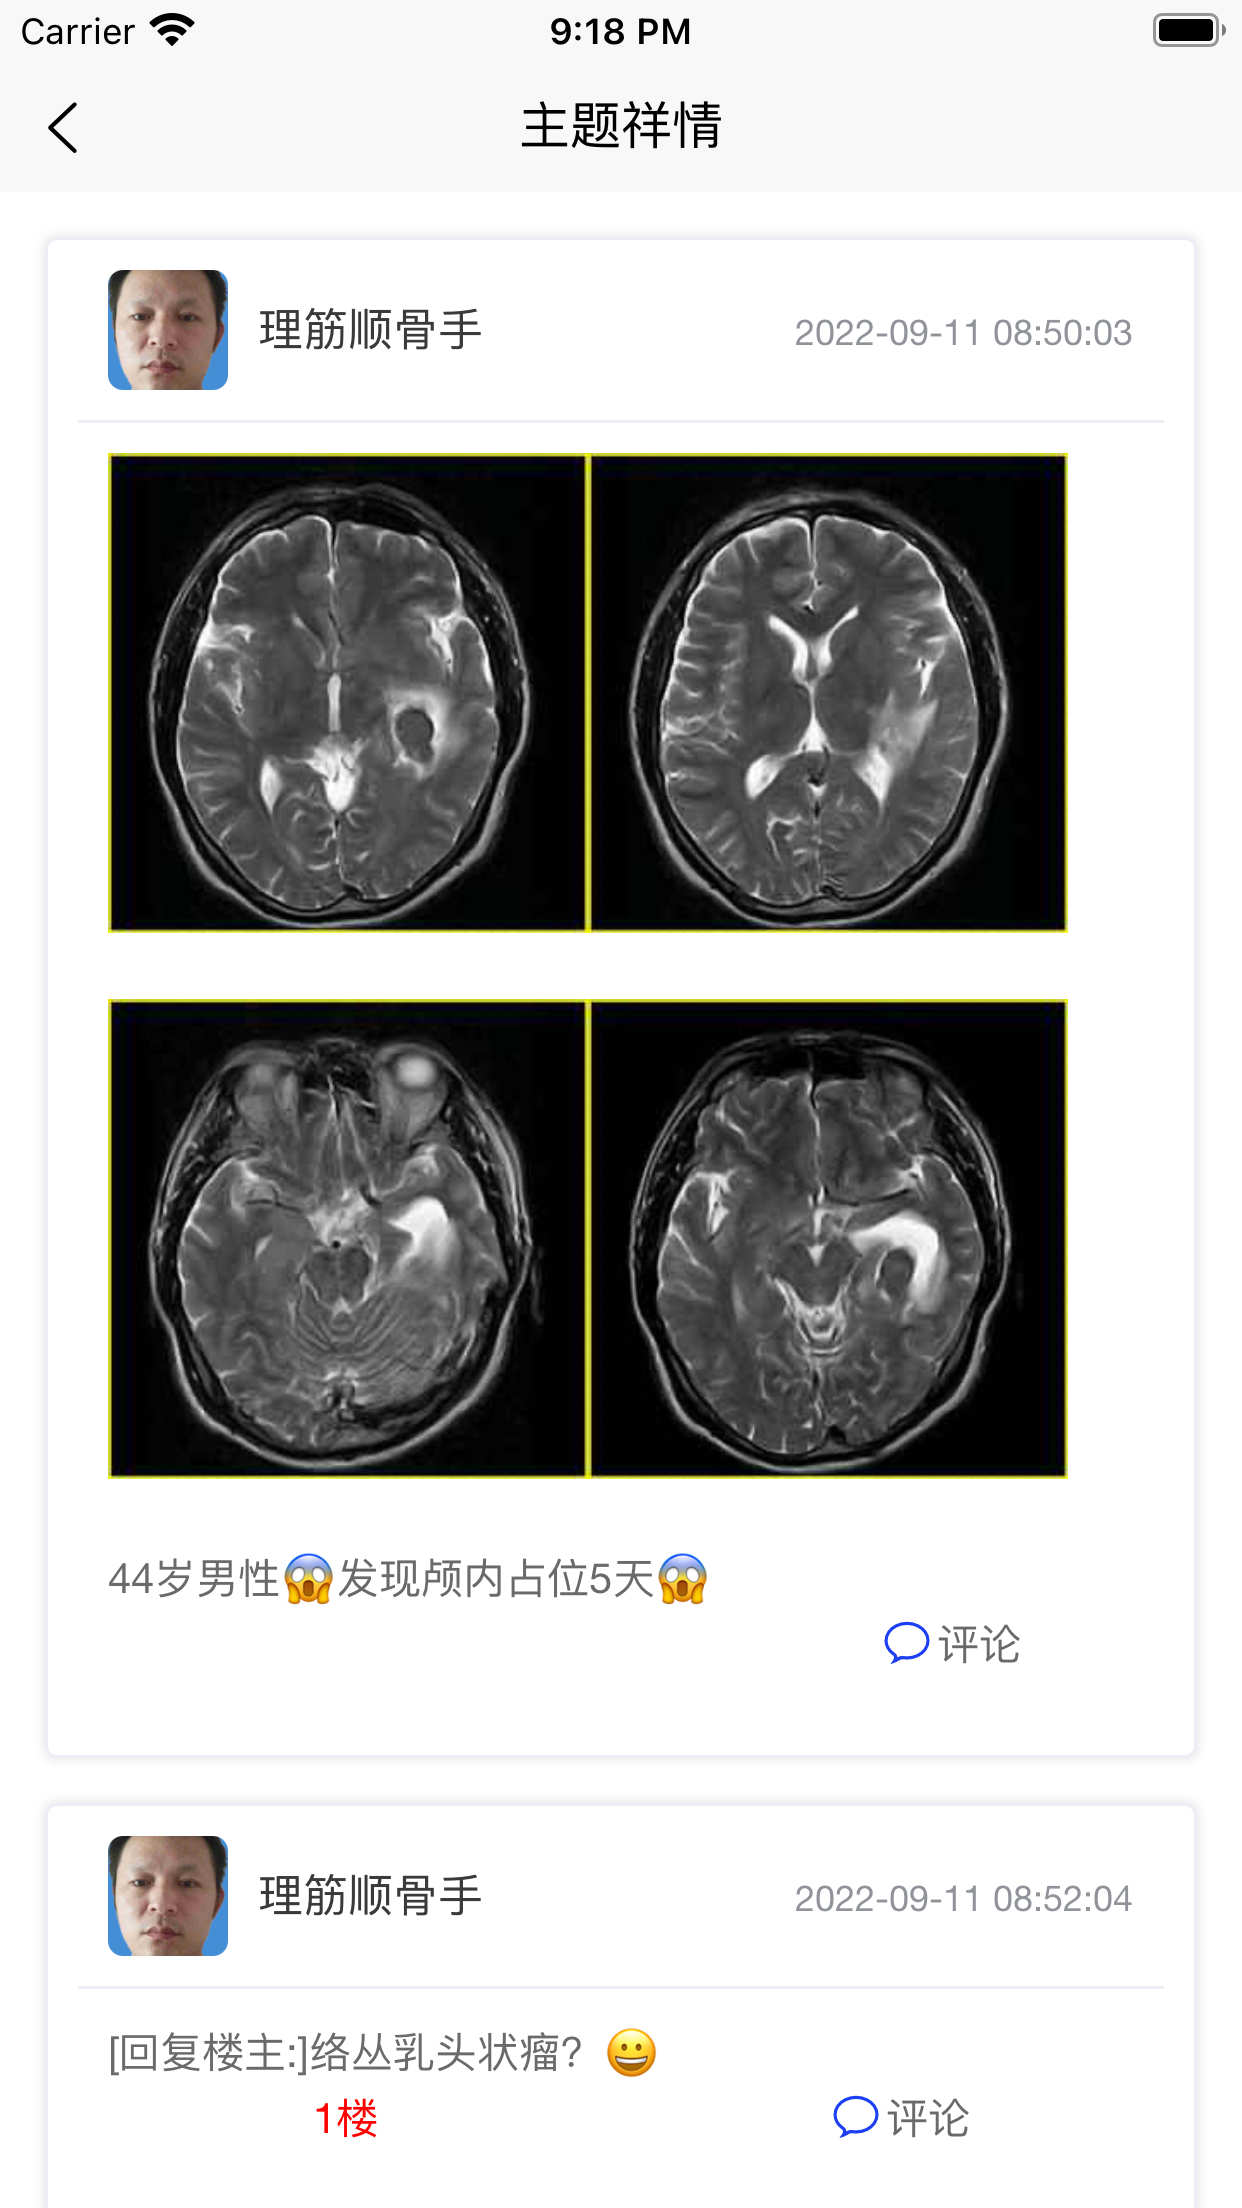

图片类主题祥情页面

此页显示图片类主题祥情,包括评论互动。